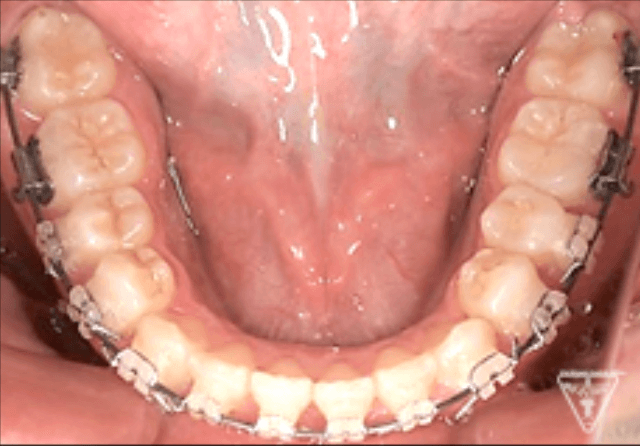

矯正器具 装着時の治療過程

治療期間・治療費・リスク

| 治療期間 | 1年 |

| 治療費 | ¥880,000 |

- 矯正装置除去後に後戻りすることがあるので、保定装置を決められた期間確実に装着してください。

- リコールによる継続定期検診が必要となります。